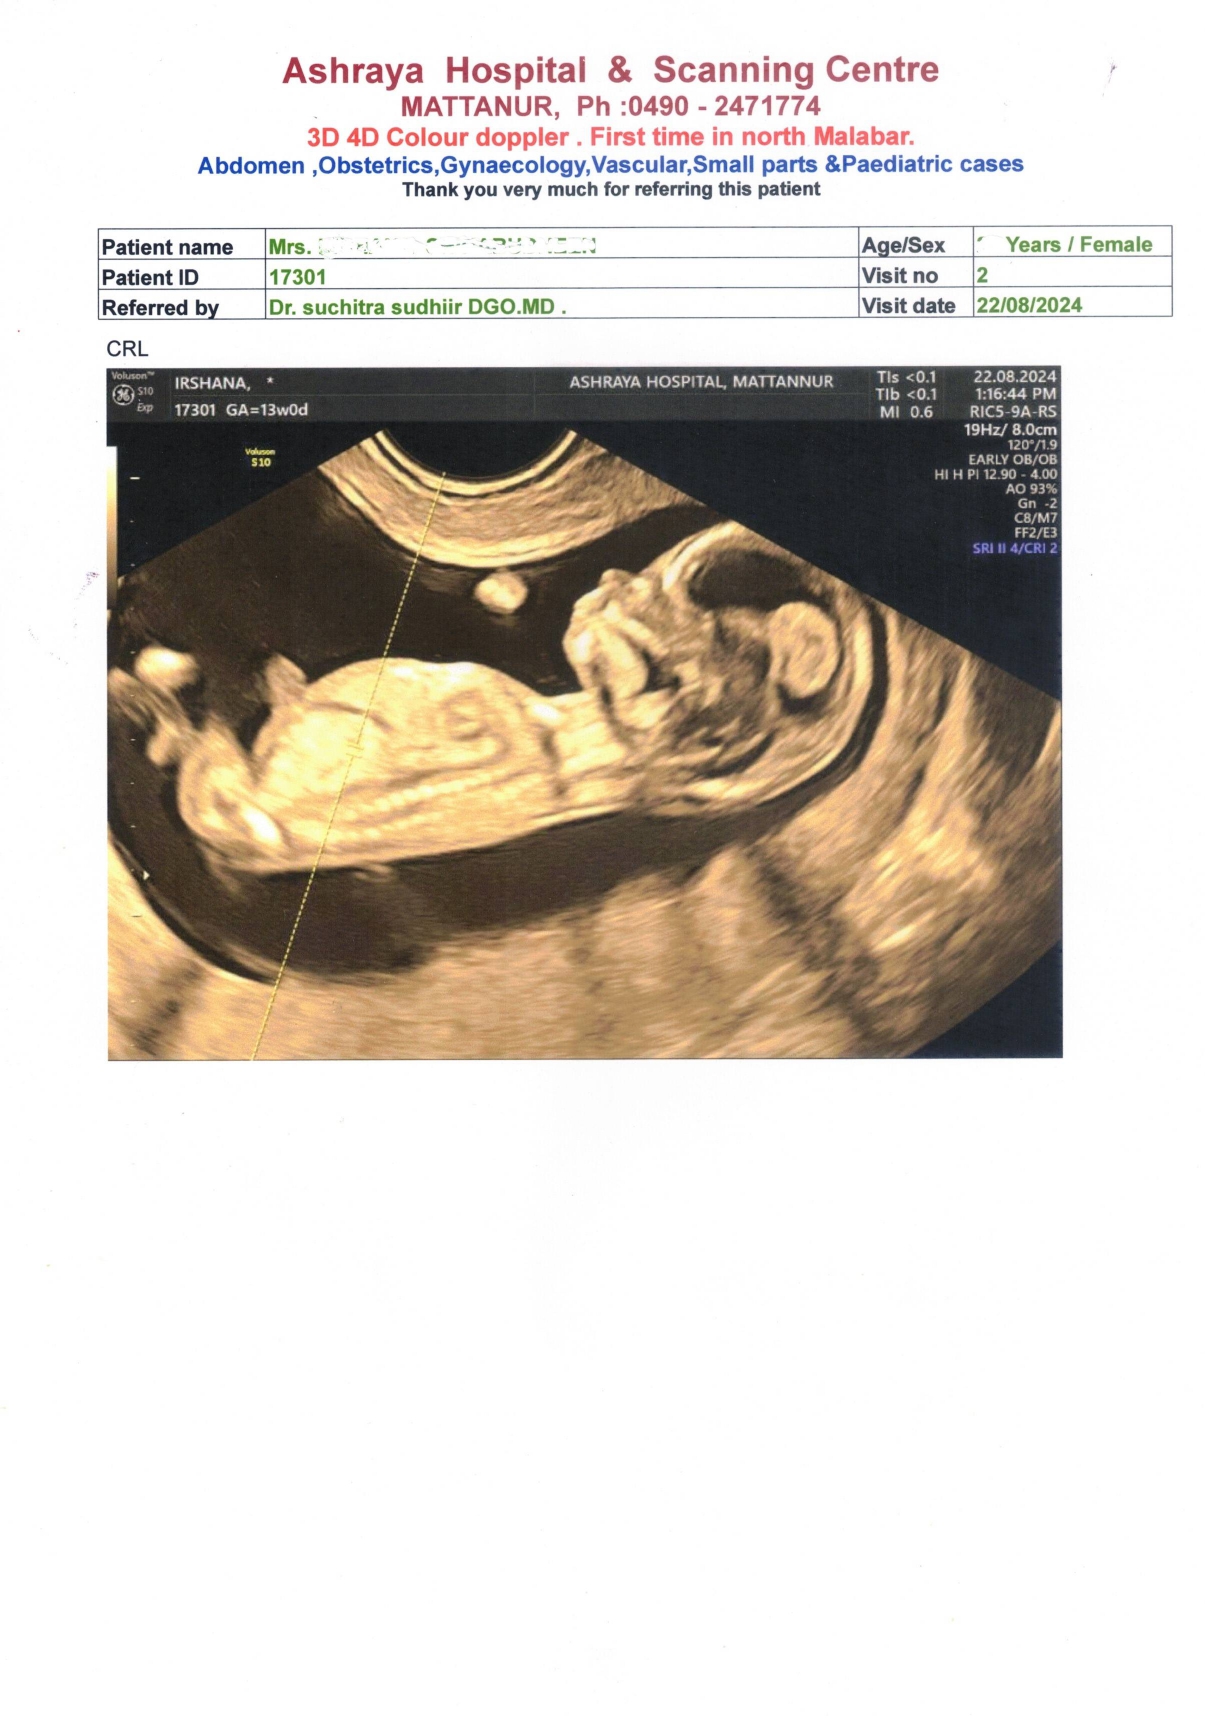

REPORT OF 13 WEEKS FETAL DONE AT ASHRAYA